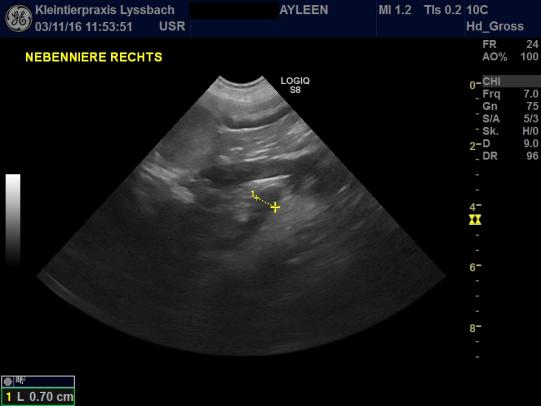

Der körperliche Untersuch von Ayleen verläuft unauffällig. Für das Leitsymptom "PU/PD" (Polyurie/Polydipsie = zuviel Urin absetzen/zuviel trinken) gibt es eine ganze Reihe von Ursachen, weshalb weitere Abklärungen angestellt werden: Eine Blutentnahme zeigt, dass Ayleen weder an einer Zuckerkrankheit, noch an einem Nierenproblem oder einer Erhöhung des Calciumspiegels leidet. Einzig ein spezifischer Leberwert ist erhöht, welcher häufig bei einer Nebennierenüberfunktion ansteigt. Ein entsprechender Test zeigt, dass die Nebennieren von Ayleen viel zuviel Cortison produzieren. Mittels Ultraschall werden die Nebennieren vermessen - die linke Nebenniere ist leicht vergrössert; die rechte Niere ist grössenmässig im oberen Grenzbereich. Es besteht der dringende Verdacht, dass Ayleen an einem sogenannten "hypophysären Cushingsyndrom" leidet - bei dieser Krankheit scheidet ein kleiner Tumor in der Hirnanhangsdrüse zuviel Steuerungshormon ACTH aus, welches die Nebennieren viel zuviel Cortison bilden lässt. Diese Form des Cushingsyndromes ist deutlich häufiger als die Nebennierenform, bei der ein Nebennierentumor zuviel Hormon produziert (siehe Fall des Monats Nr. 83 ).